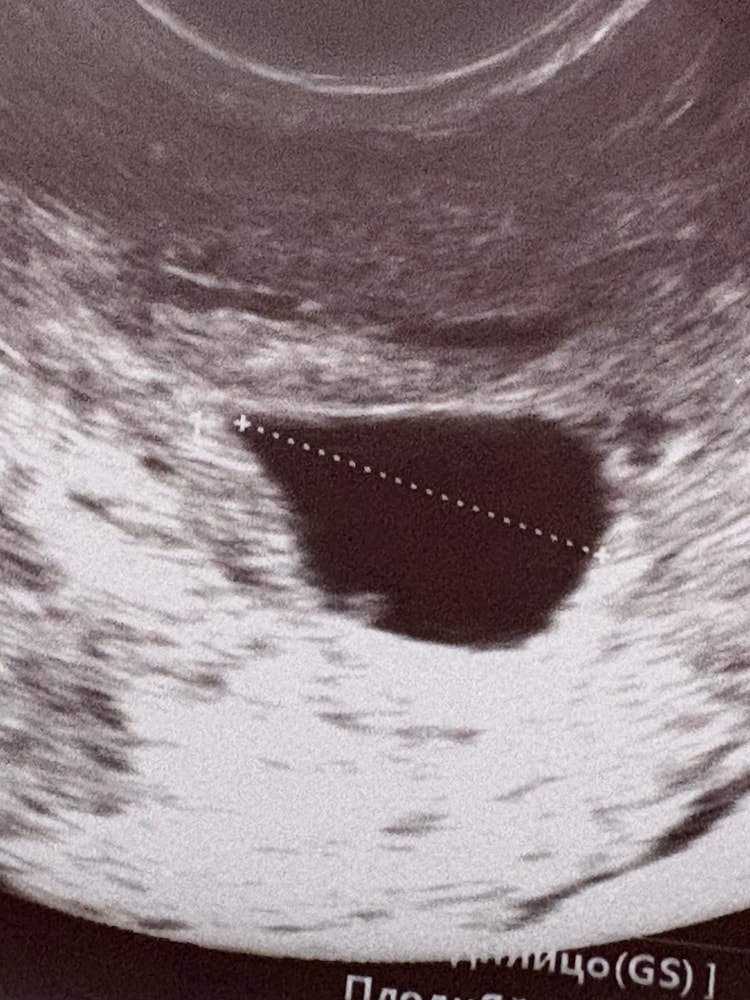

УЗИ, КТГ, доплерПервое узи было в 6.1 по М, увидели ПЯ 15мм, ЖМ 4мм и предположительно эмбрион 5мм (в платной), в ЖК в 6.5 увидели только ПЯ 20мм (узист быстро смотрела, да и мне ничего не показала на экране). Так бывает, что за 4 дня все пропадает?😅 ссылаюсь к тому, что узист в ЖК не очень. Завтра (7.1 по М будет) пойду в платную снова на узи. ХГЧ рос хорошо:

Марина, в той платной аппарат среднего класса был, а в ЖК высокого считается. Нет, сб не увидели из-за аппарата, но вот что получилось на узи в 6.1

Такая фотка получилась в этот раз